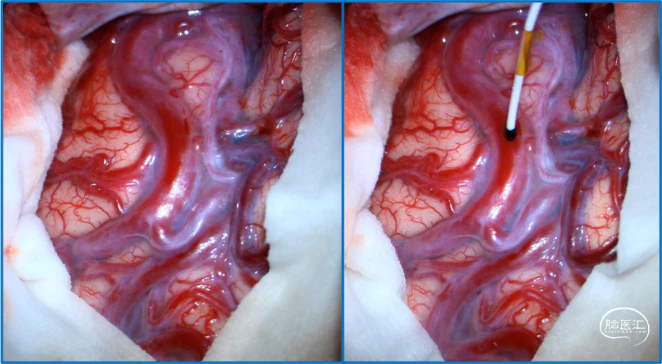

典型病例

![]()

神经内镜可以辅助确认颞极深部的引流静脉,避免残留引流静脉。